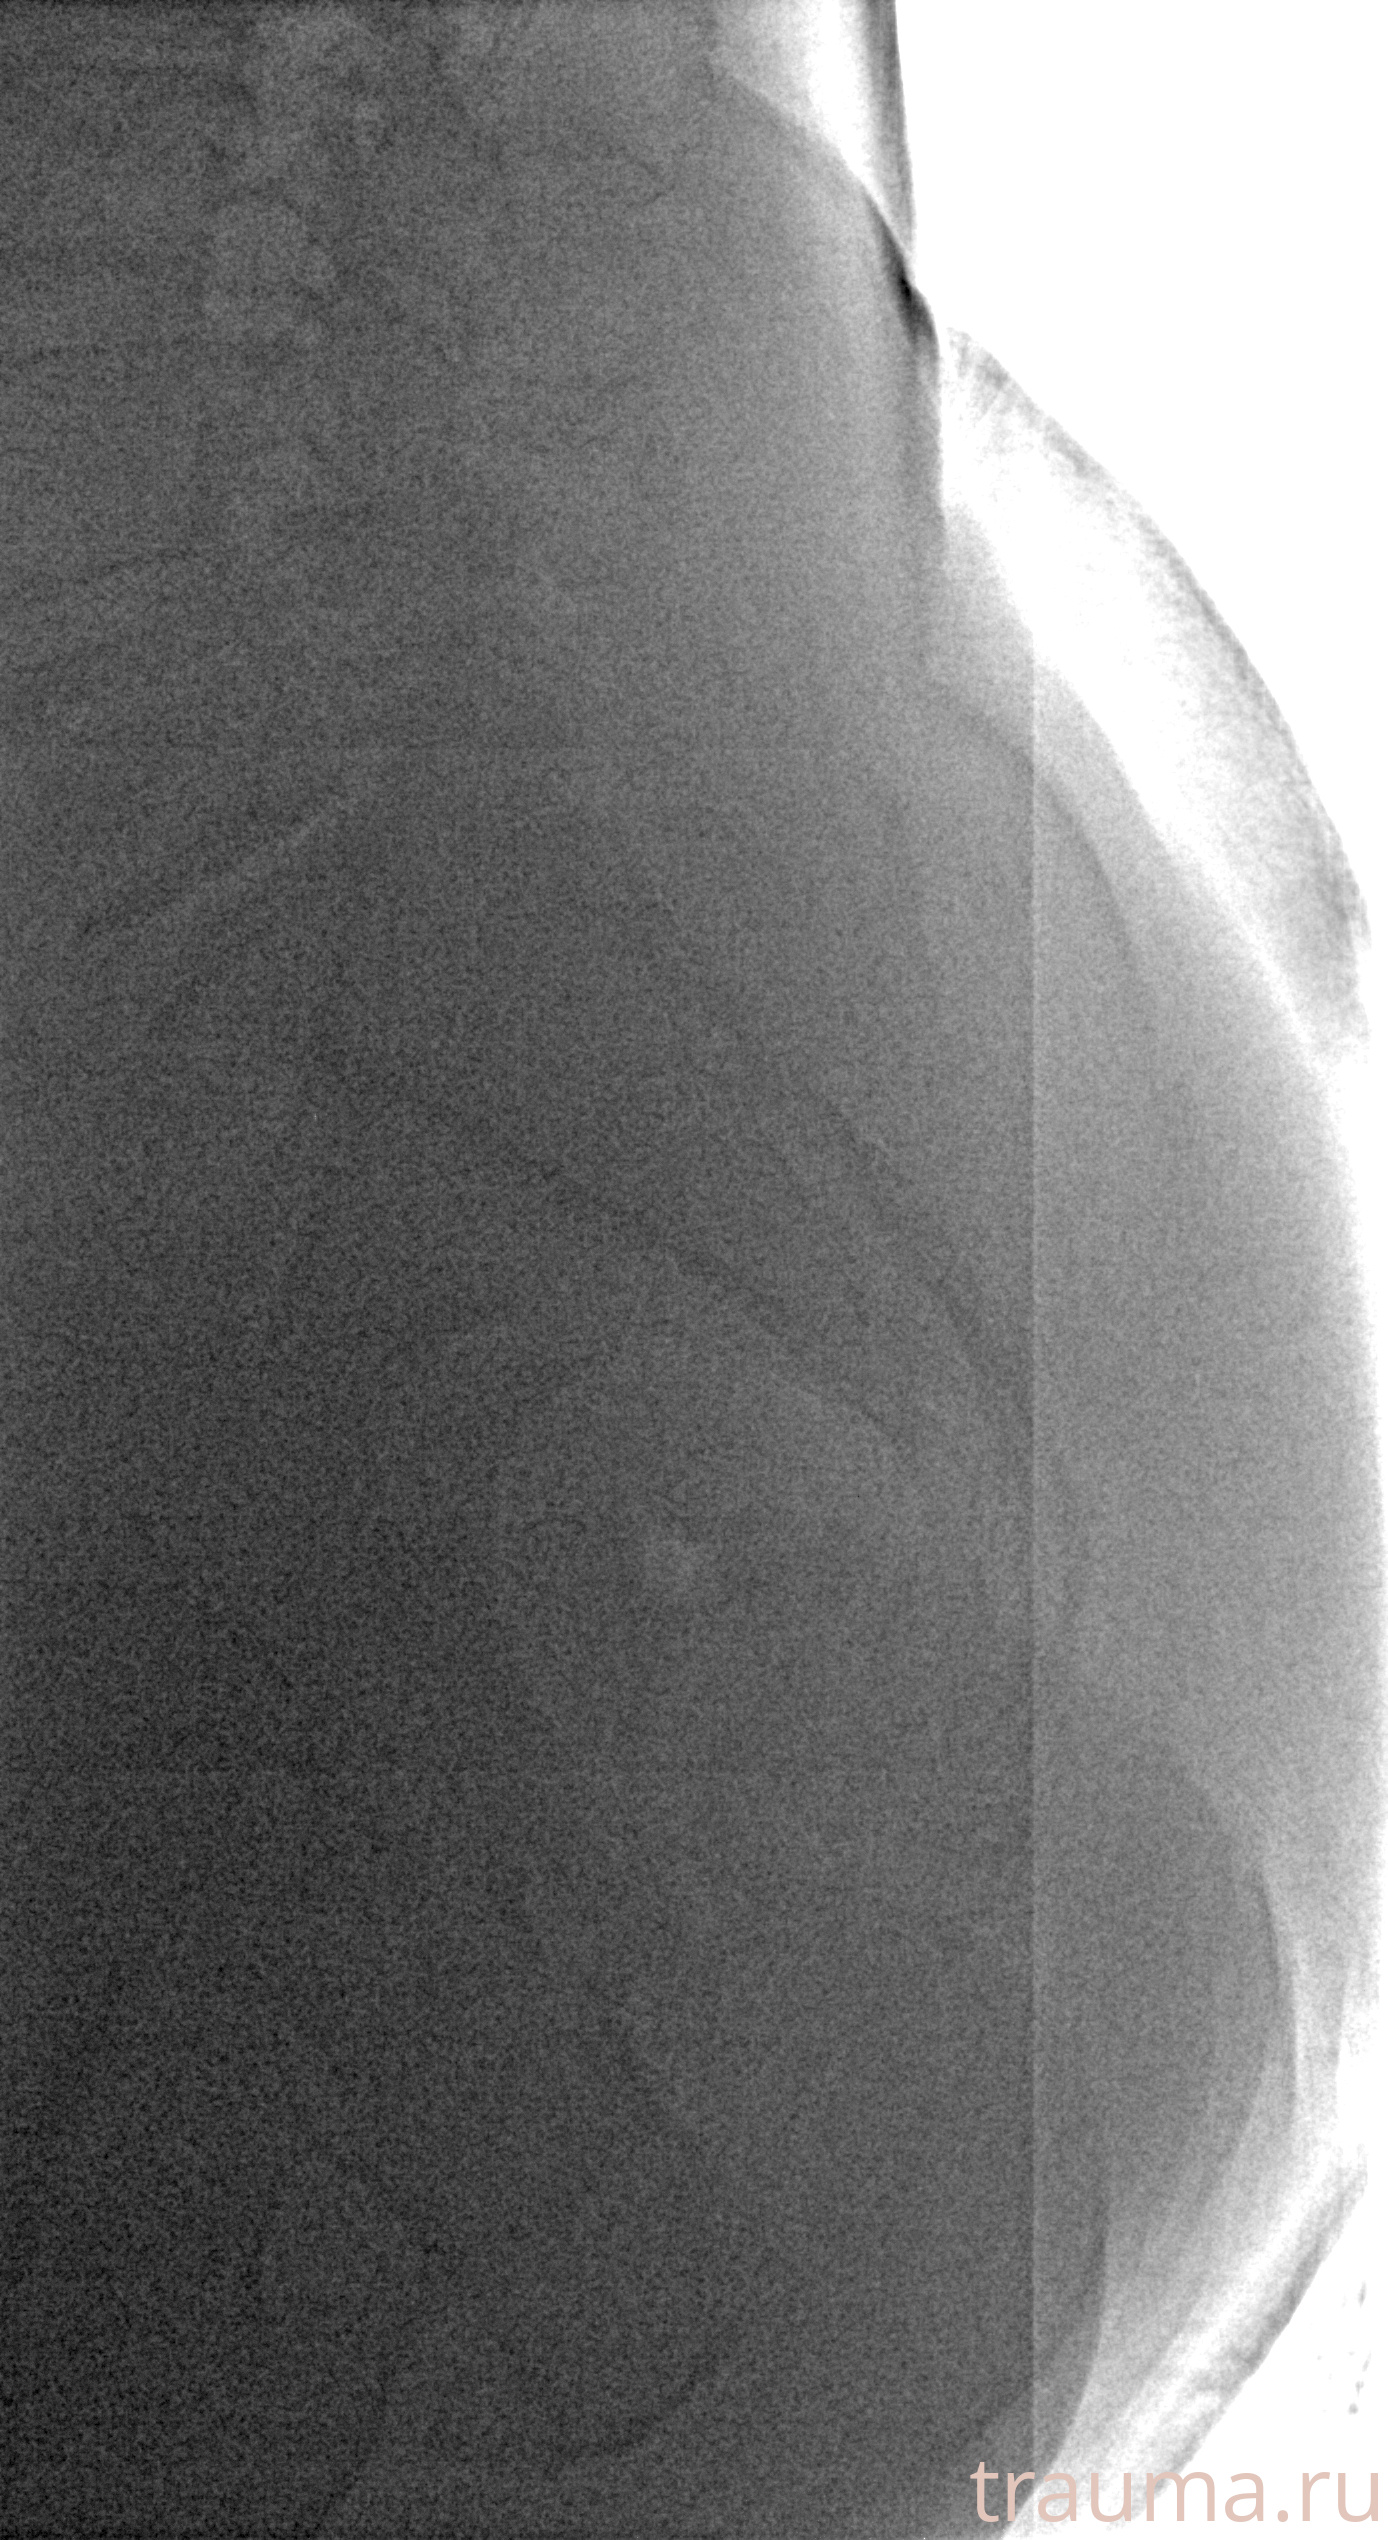

Рентгенограммы

Рентген на дому: по вашему адресу приезжает врач-рентгенолог, травматолог-ортопед с мобильным рентгеновским аппаратом, проводит диагностику травмы или заболевания, делает необходимые рентгенограммы, дает рекомендации по дальнейшему лечению. Получить качественные снимки в домашних условиях возможно благодаря уникальной методике, разработанной МосРентген Центром для института  Склифосовского

Яркость: 1   Контраст: 1   Инвертировать: 0 Увеличение: 1

Перетаскивайте мышь вверх/вниз для контраста, влево/право для яркости. Прокрутка колесом изменяет масштаб. Нажмите Сбросить для возврата к исходному изображению. При увеличении держите мышь в той области, которую хотите рассмотреть.